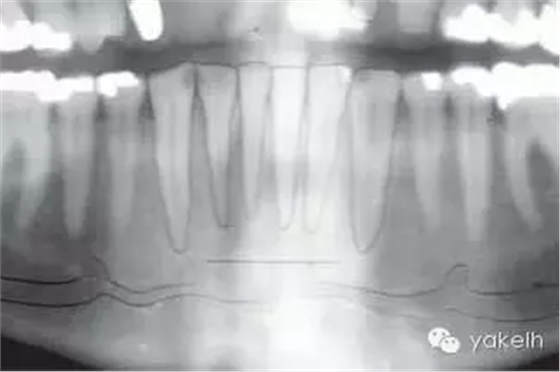

¤¤與口腔頜面部的其他供區(qū)相比,頦部術(shù)后并發(fā)癥的發(fā)生率更高。當(dāng)骨塊以及環(huán)形骨塊移除后,下前牙感覺異常是術(shù)后常見并發(fā)癥。如切牙管神經(jīng)在取骨過程中受損(圖13.24,圖13.25),患者會(huì)感到切牙感覺異常,該損傷通常在6個(gè)月內(nèi)可以自行修復(fù),此時(shí)前牙通常不需要做根管治療。但也會(huì)發(fā)生由于牙髓受損,導(dǎo)致下切牙變色或者繼發(fā)性牙本質(zhì)形成(圖13.26)。即使于前庭溝處做切口,也可出現(xiàn)頦部神經(jīng)感覺異常。骨移植患者發(fā)生頦神經(jīng)感覺異常的幾率較低,但是也有高達(dá)43%的并發(fā)癥發(fā)生率報(bào)道(13.27)。在寒冷的天氣時(shí),頦部氣候功能癥也有報(bào)道。盡管大多數(shù)受損的患者可恢復(fù)正常,但是仍給患者造成困擾。術(shù)前討論可能的并發(fā)癥是明智的,這包括手術(shù)會(huì)導(dǎo)致牙齒以及頦部感覺的異常。盡管未有術(shù)后頦部軟組織外形改變的報(bào)道,但患者往往擔(dān)心該區(qū)域取骨后是否會(huì)影響美觀。影像學(xué)證據(jù)表明,在一些老年患者中,供區(qū)骨空腔不能完全修復(fù)。用可吸收的骨替代品,如骨庫骨或者小牛骨充填供區(qū)的缺損,可以減少患者的疑慮。術(shù)后沒有發(fā)生過頦部下垂,但為防止頦部下垂,在取骨時(shí)應(yīng)避免把下頜骨上的組織完全撕脫。曾有報(bào)道在取骨后,下頜骨剩余舌側(cè)骨板發(fā)生骨折。如前所述,這可能是取骨時(shí),太靠近下頜骨邊緣所造成的。頦部取骨的術(shù)后疼痛比較明顯。術(shù)后應(yīng)用長(zhǎng)效局麻藥,如布比卡因行下頜神經(jīng)阻滯麻醉,可以延遲疼痛的發(fā)生,以便人體有充分的時(shí)間來吸收止痛藥。術(shù)前應(yīng)用非甾體類藥物,如布洛芬等可減少疼痛和腫脹。

圖13.24 全景片提示切牙管的位置。

圖13.25 在頦部取骨過程中,經(jīng)常損傷到下齒槽神經(jīng)的切牙分支。